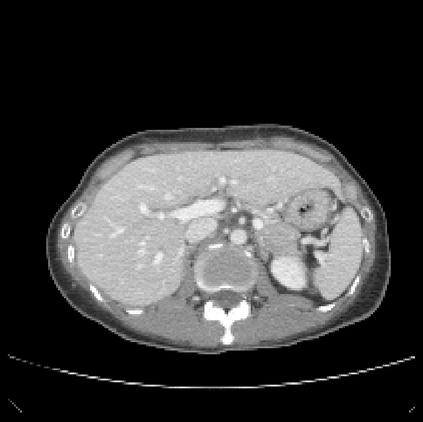

It is imperative to ensure the robustness of deep learning models in critical applications such as, healthcare. While recent advances in deep learning have improved the performance of volumetric medical image segmentation models, these models cannot be deployed for real-world applications immediately due to their vulnerability to adversarial attacks. We present a 3D frequency domain adversarial attack for volumetric medical image segmentation models and demonstrate its advantages over conventional input or voxel domain attacks. Using our proposed attack, we introduce a novel frequency domain adversarial training approach for optimizing a robust model against voxel and frequency domain attacks. Moreover, we propose frequency consistency loss to regulate our frequency domain adversarial training that achieves a better tradeoff between model's performance on clean and adversarial samples. Code is publicly available at https://github.com/asif-hanif/vafa.